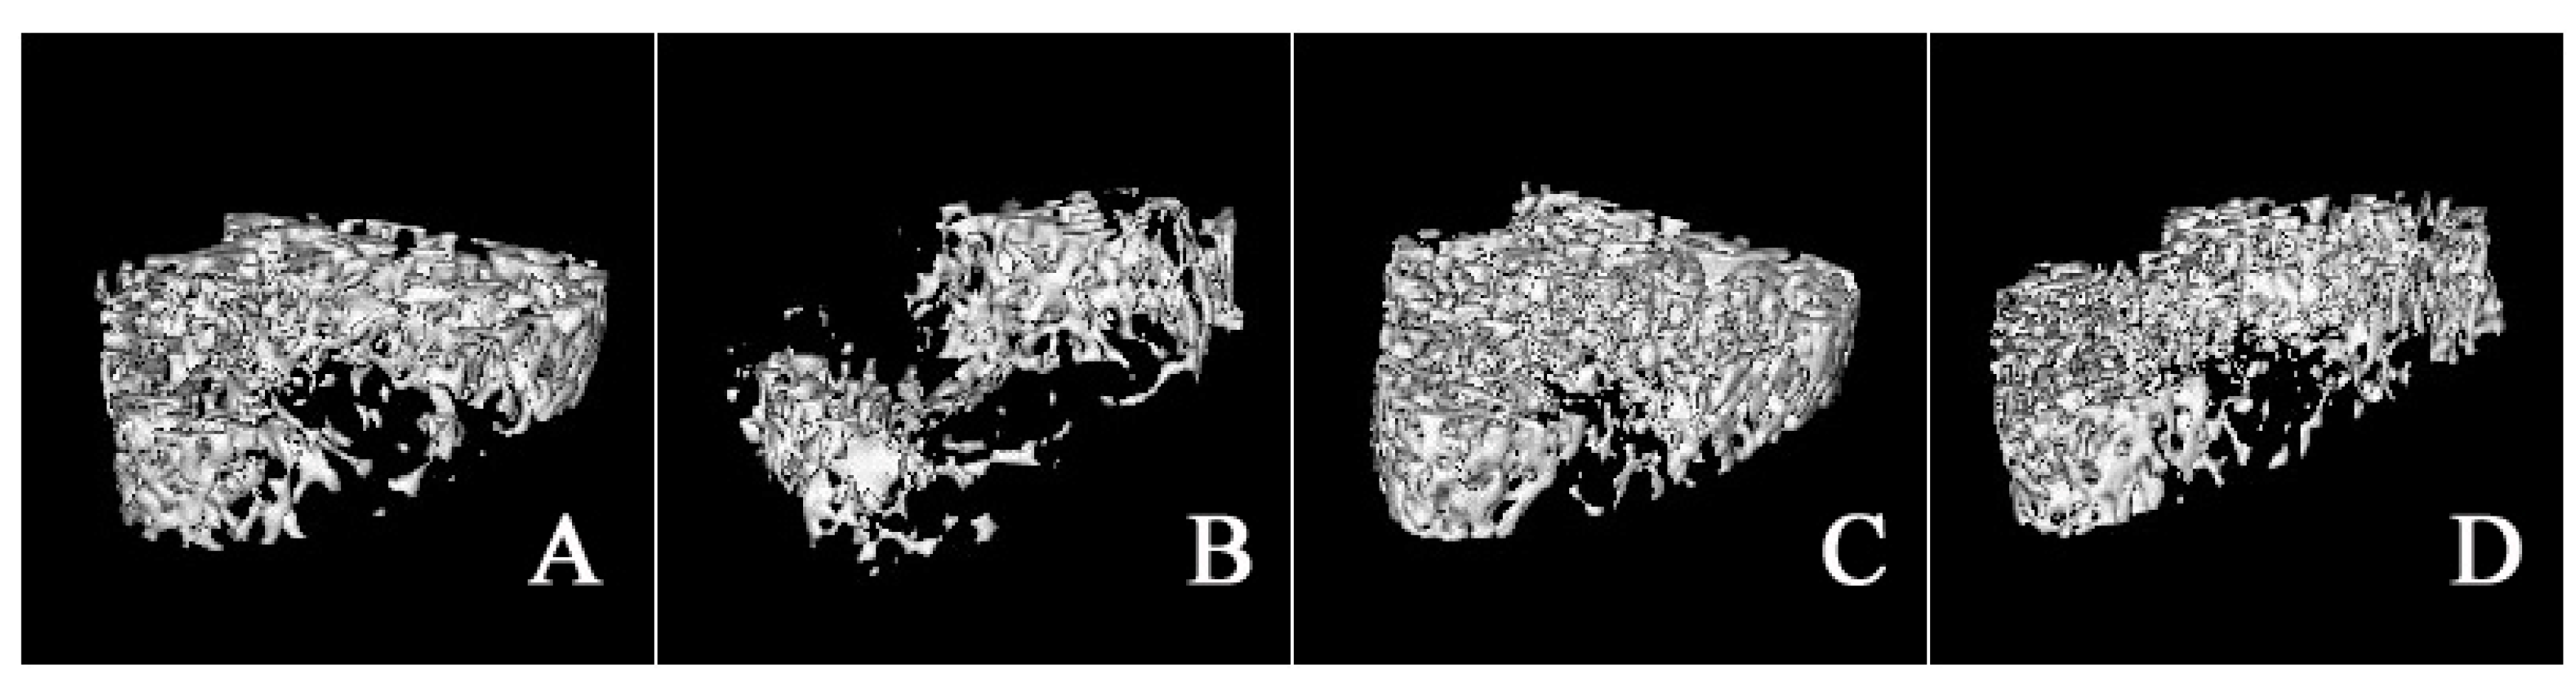

HLS generated a deteriorated condition of femoral trabecula according to the 3-D images or the corresponding architectural parameters of a MicroCT assay [15]. Representative 3-D images of trabecular bone within various treatment groups are shown in Figure 3. Micro-architecture properties of femoral trabecula were analyzed by the microCT Evaluation Program (V2.1.2, GE healthcare, Madison, WI, USA) and the results were shown in Figure 4. Compared with the CON group, hindlimb suspension could significantly decrease BV/TV (−30.70%), Tb.Th (−16.37%), Tb.N (−34.11%), and Conn. D (−32.20%), whereas Tb.Sp was increased by 76.51%. In addition, cortical thickness was not influenced by HLS or drug treatment.

Figure 3.

Representative 3-D images of bone trabeculain the distal femoral metaphysic region: (A) CON; (B) HLS; (C) HLS-ALE; (D) HLS-RSE (n = 6). CON: control group; HLS: hindlimb suspended group; HLS-ALE: group administrated with alendronate (2 mg/kg/day); HLS-RSE: group administrated with Radix Scutellariae extract (50 mg/kg/day).

By comparing the micro-architecture properties of trabecular femur between both genders, hindlimb suspension generated greater decrease in BV/TV (−77.60%), Tb.Th (−31.17%), Tb.N (−70.43%), and Conn. D (−99.13%) for male rats. The enhancement in Tb.Sp was also greater in male rats (295.04%). For both genders, ALE and RSE treatment significantly improved the impaired micro-architecture parameters induced by hindlimb suspension (p < 0.01) [14].